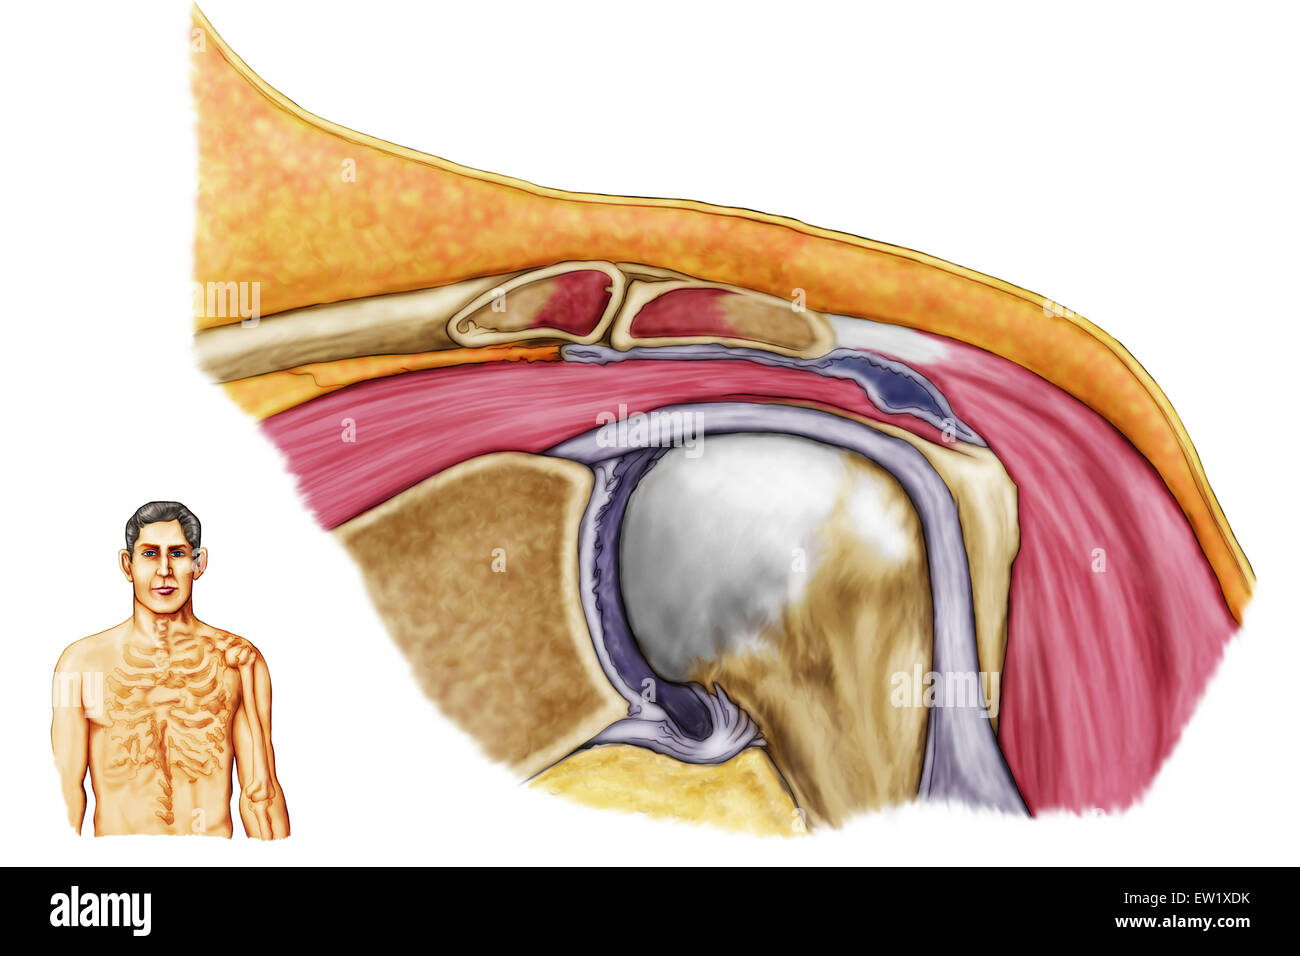

Anatomy of left shoulder, coronal view. Stock Photohttps://www.alamy.com/image-license-details/?v=1https://www.alamy.com/stock-photo-anatomy-of-left-shoulder-coronal-view-84250591.html

Anatomy of left shoulder, coronal view. Stock Photohttps://www.alamy.com/image-license-details/?v=1https://www.alamy.com/stock-photo-anatomy-of-left-shoulder-coronal-view-84250591.htmlRFEW1XDK–Anatomy of left shoulder, coronal view.